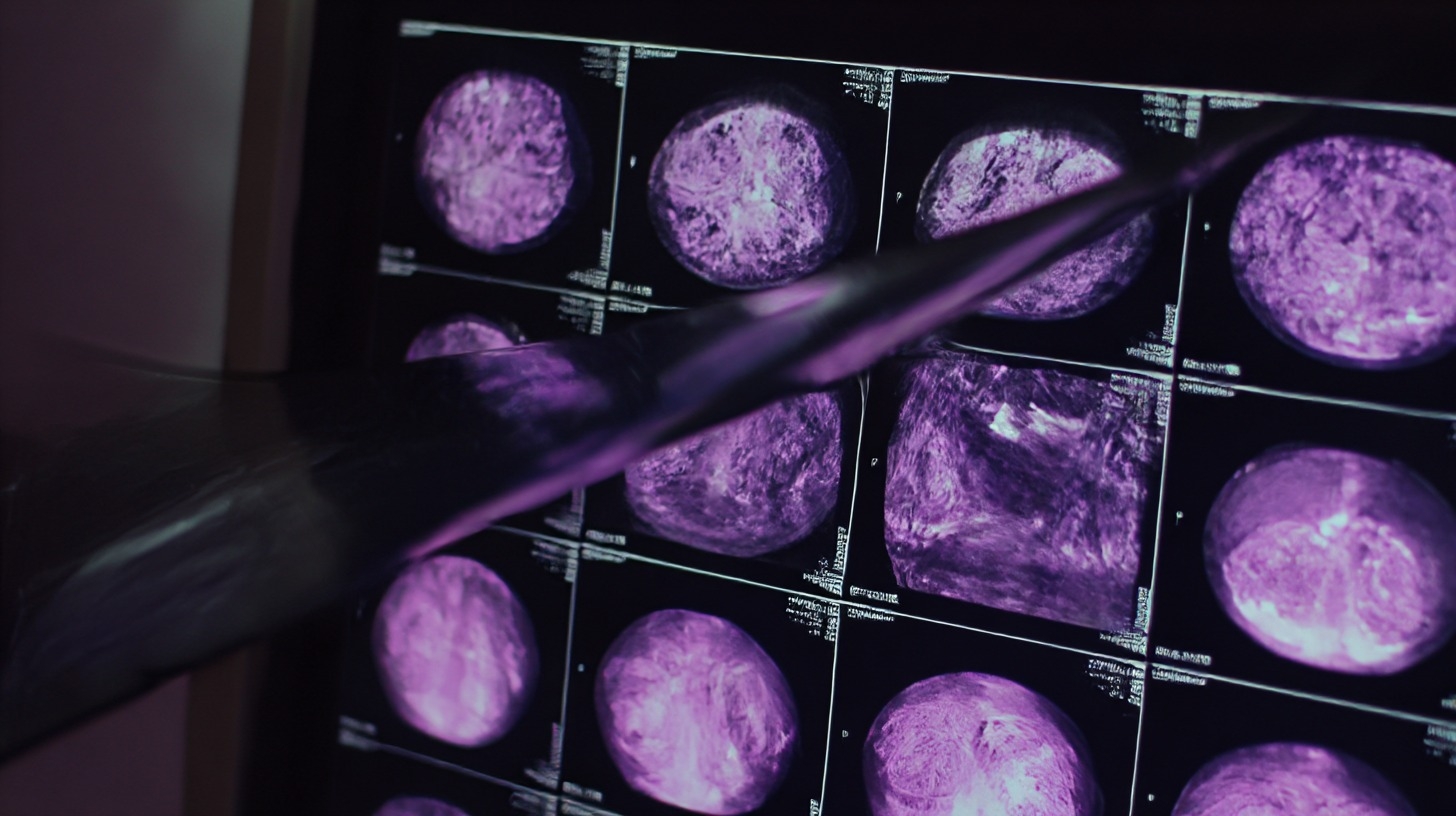

radiographie

Pour le Professeur Pujol, il y a urgence à "être conscient de la hausse de l'incidence". Sans forcément généraliser la mammographie, qui peut être moins pertinente chez les femmes jeunes, il appelle à un "dépistage personnalisé renforcé" (échographie, IRM) et à une plus grande vigilance des médecins face à une "boule dans le sein" chez une patiente de moins de 40 ans.